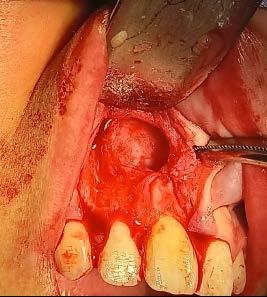

54 | ENCICLOPEDIA ODONTOLÓGICA

Terapéutica endoquirúrgica para periodontitis apical crónica: reporte de un caso